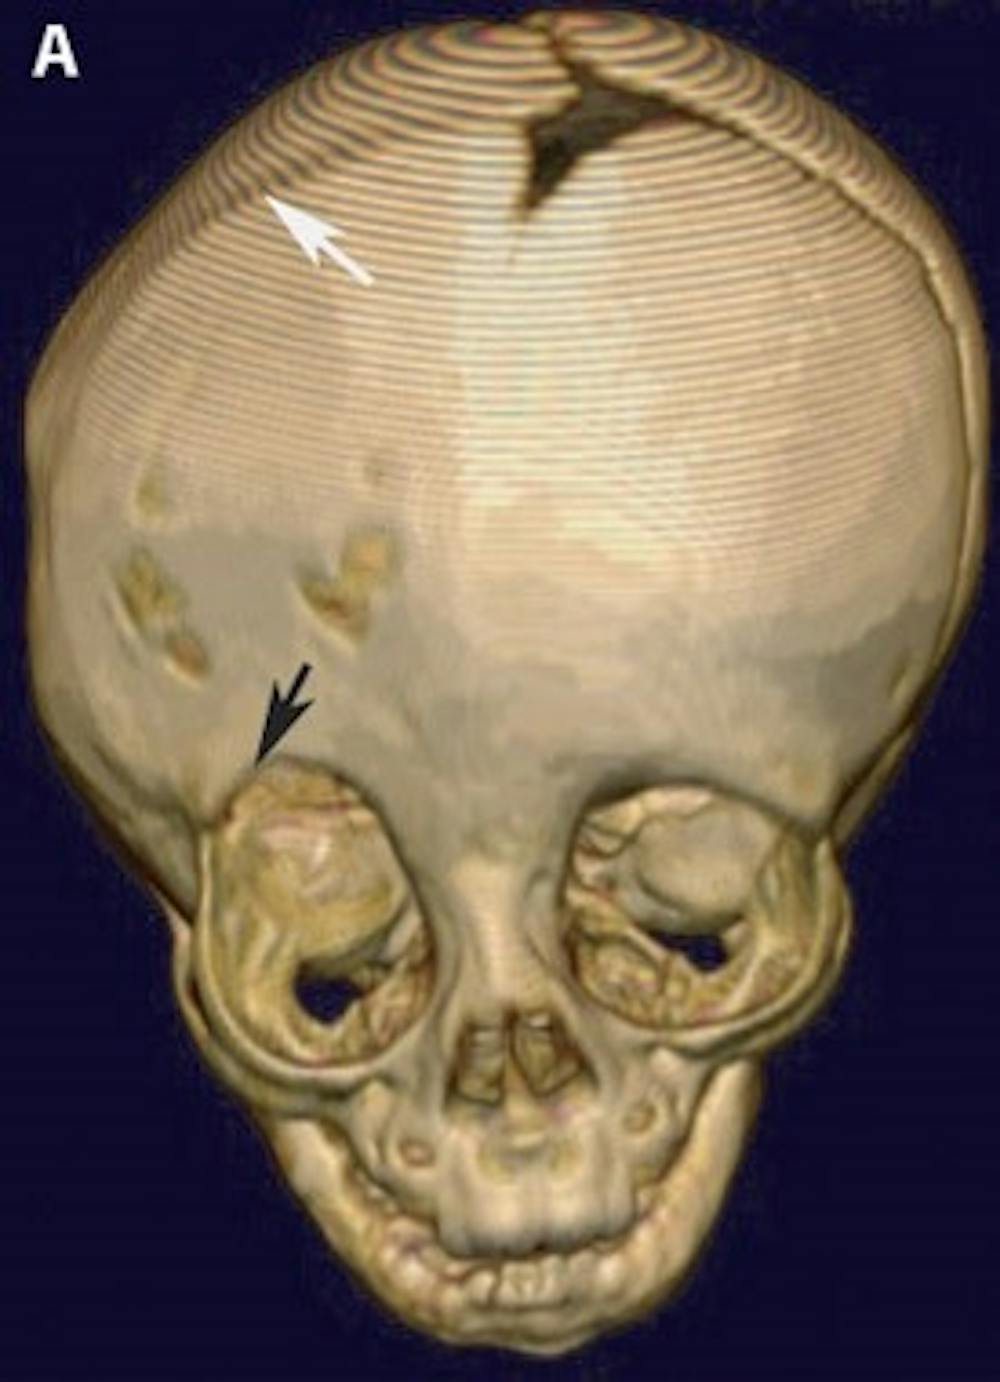

A) Pre-operative 3-D CT reconstruction of the skull demonstrating the effects of craniosynostosis. Note how the premature fusion of the right coronal suture (white arrow) has led to a distortion of the overall shape of the skull and right orbit (black arrow)